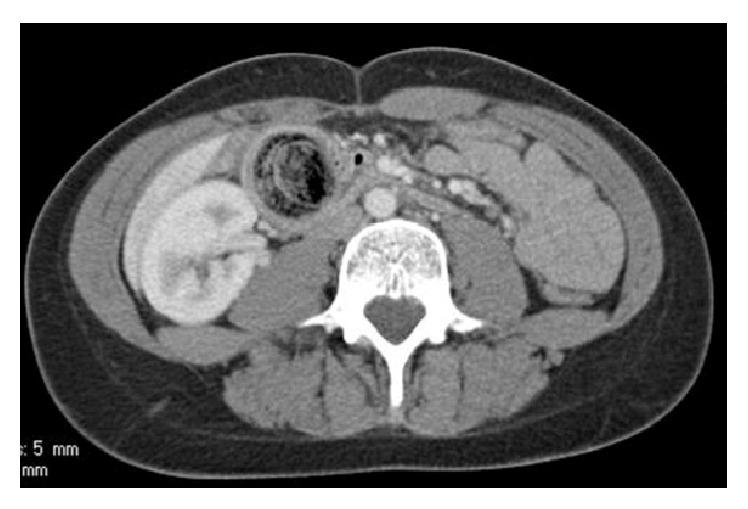

A 17-year-old girl presented with bilious vomiting and abdominal pain to the surgery department. The history was positive for trichotillomania and trichophagia. A CT scan showed a mass in the stomach, which was highly suspicious for a gastric bezoar. Drooping parts of the bezoar caused a duodenal obstruction with secondary acute pancreatitis. The bezoar was removed via a laparoscopically performed gastrotomy.

一名17岁女孩因胆汁性呕吐和腹痛就诊于外科。病史显示有拔毛癖和食毛症。CT扫描显示胃内有一肿块,高度怀疑为胃石。胃石下垂部分导致十二指肠梗阻并继发急性胰腺炎。通过腹腔镜胃切开术取出了胃石。